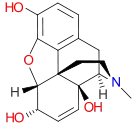

Dihydrocodeine series

Active opiate metabolites

- Codeine-6-glucuronide

- Codeine-N-oxide (genocodeine)

- Heroin-7,8-oxide

- Morphine-6-glucuronide

- 3-Monoacetylmorphine

- 6-Monoacetylmorphine

- Morphine-N-oxide (genomorphine)

- Naltrexol

- Norcodeine

- Normorphine

Structures

| Active opiate metabolites | ||||

Codeine-N-oxide Codeine-N-oxide |

Heroin-7,8-oxide Heroin-7,8-oxide |

Morphine-6-glucuronide Morphine-6-glucuronide |

6-Monoacetylmorphine 6-Monoacetylmorphine | |

Morphine-N-oxide Morphine-N-oxide |

Naltrexol Naltrexol |

Norcodeine Norcodeine |

Normorphine Normorphine | |